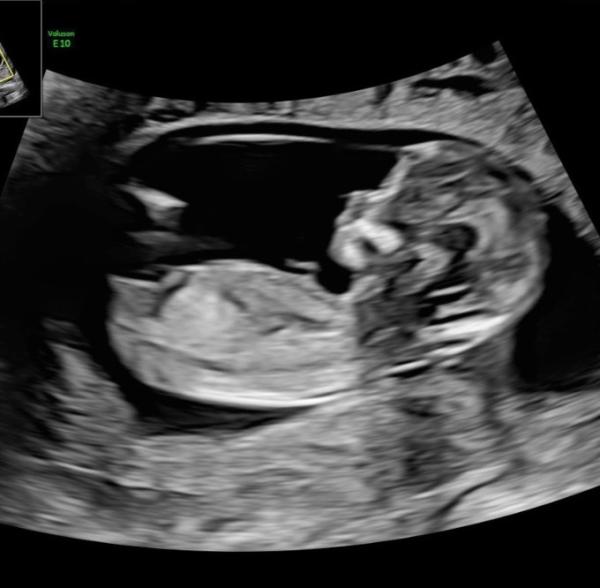

Hallo ihr Lieben, Ich habe über die NUB-Theorie gelesen, jedoch kann ich es nicht wirklich unterscheiden Was sagt ihr ? Das Bild ist auch aus der SSW 10, vielleicht ist es auch noch zu früh für diese Theorie? Lg

Ich hoffe man kann das Foto sehen?